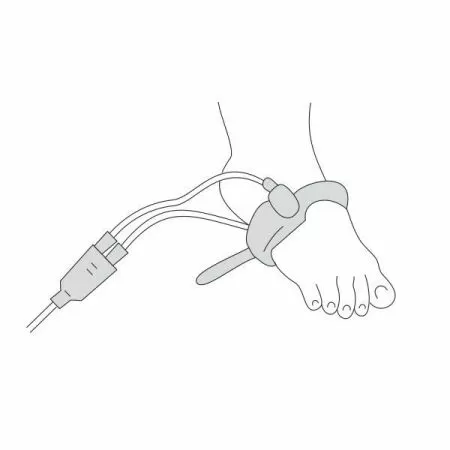

- Датчик пульсоксиметрический «Манжетка» состоит из Y-образной пары излучатель-фотоприемник и фиксирующего ремешка. Поместите излучатель и фотоприемник в разъемы фиксирующего ремешка и закрепите на пациенте.

- При этом следует следить, чтобы излучатель находился напротив фотоприемника и фотоприемник прилегал к мягким тканям.

- Не затягивайте датчик слишком сильно, чтобы не нарушить циркуляцию крови.

- Для длительного хранения датчика «Манжетка» рекомендуется максимально затянуть фиксирующий ремешок, не изымая из него излучатель и фотоприемник (Y- образную пару).